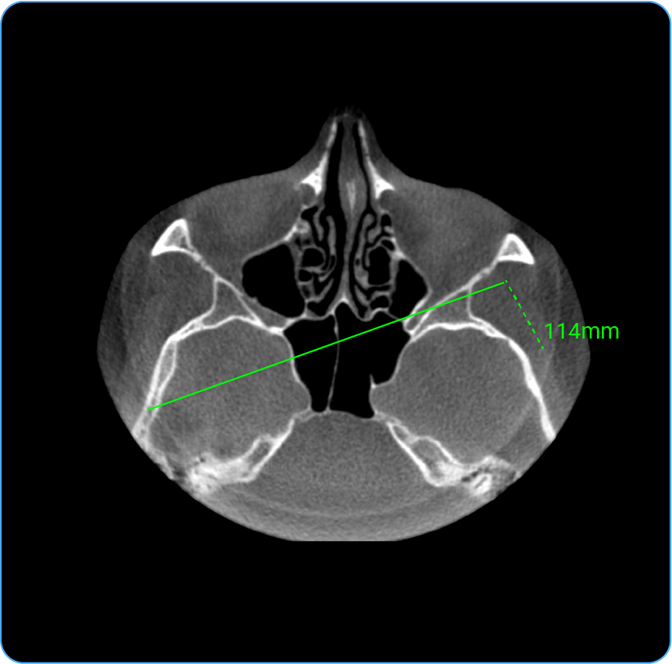

How Do I Measure Length?

• Usage: Measure distance between two points.

• Hotkey: Press D.

• Clinical Utility: Helps measure anatomical structures or lesion sizes.

• Locate the Length tool on the wheel and click on it to calculate the distance between two points on the image, useful for measuring anatomical structures.